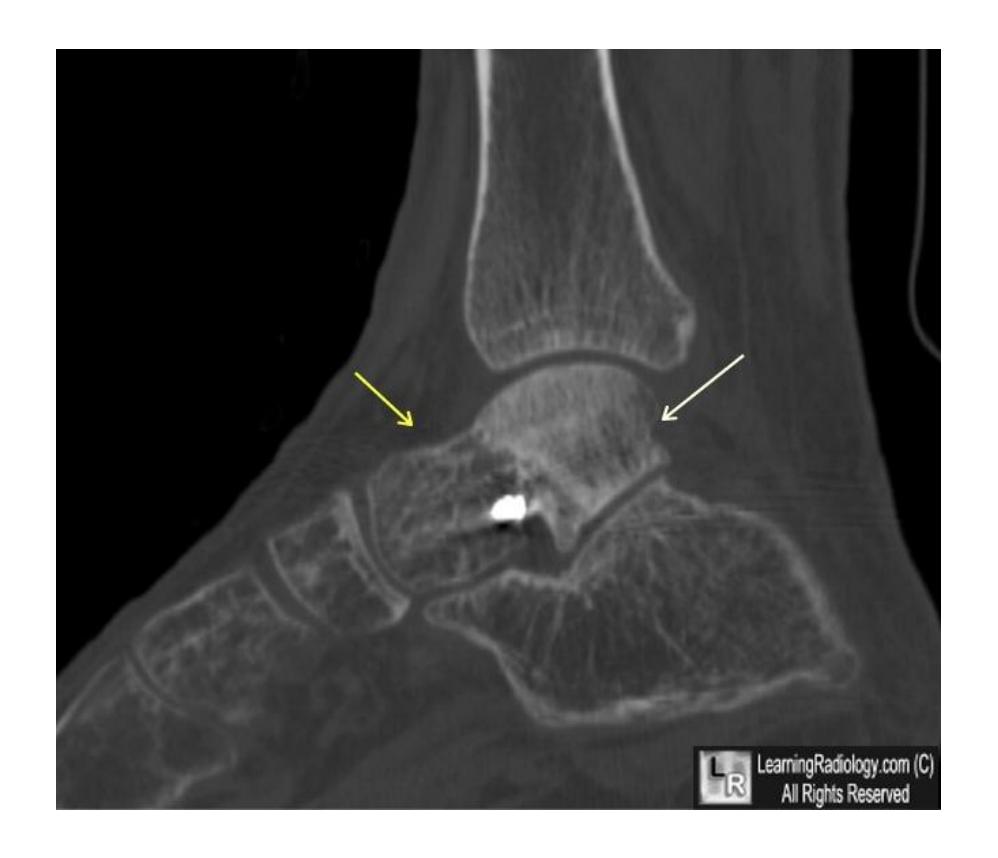

Calcaneal Fractures

Calcaneal Fracture

Complications: If displaced, can lead to osteoarthritis of subtalar joint which is painful Evaluation: CT scan to assess displacement Treatment: Conservative management

Calcaneal Fracture Evaluation

Q2: What other image you need for better evaluation of fracture?

- Calcaneal fracture

- CT scan to show the displacement